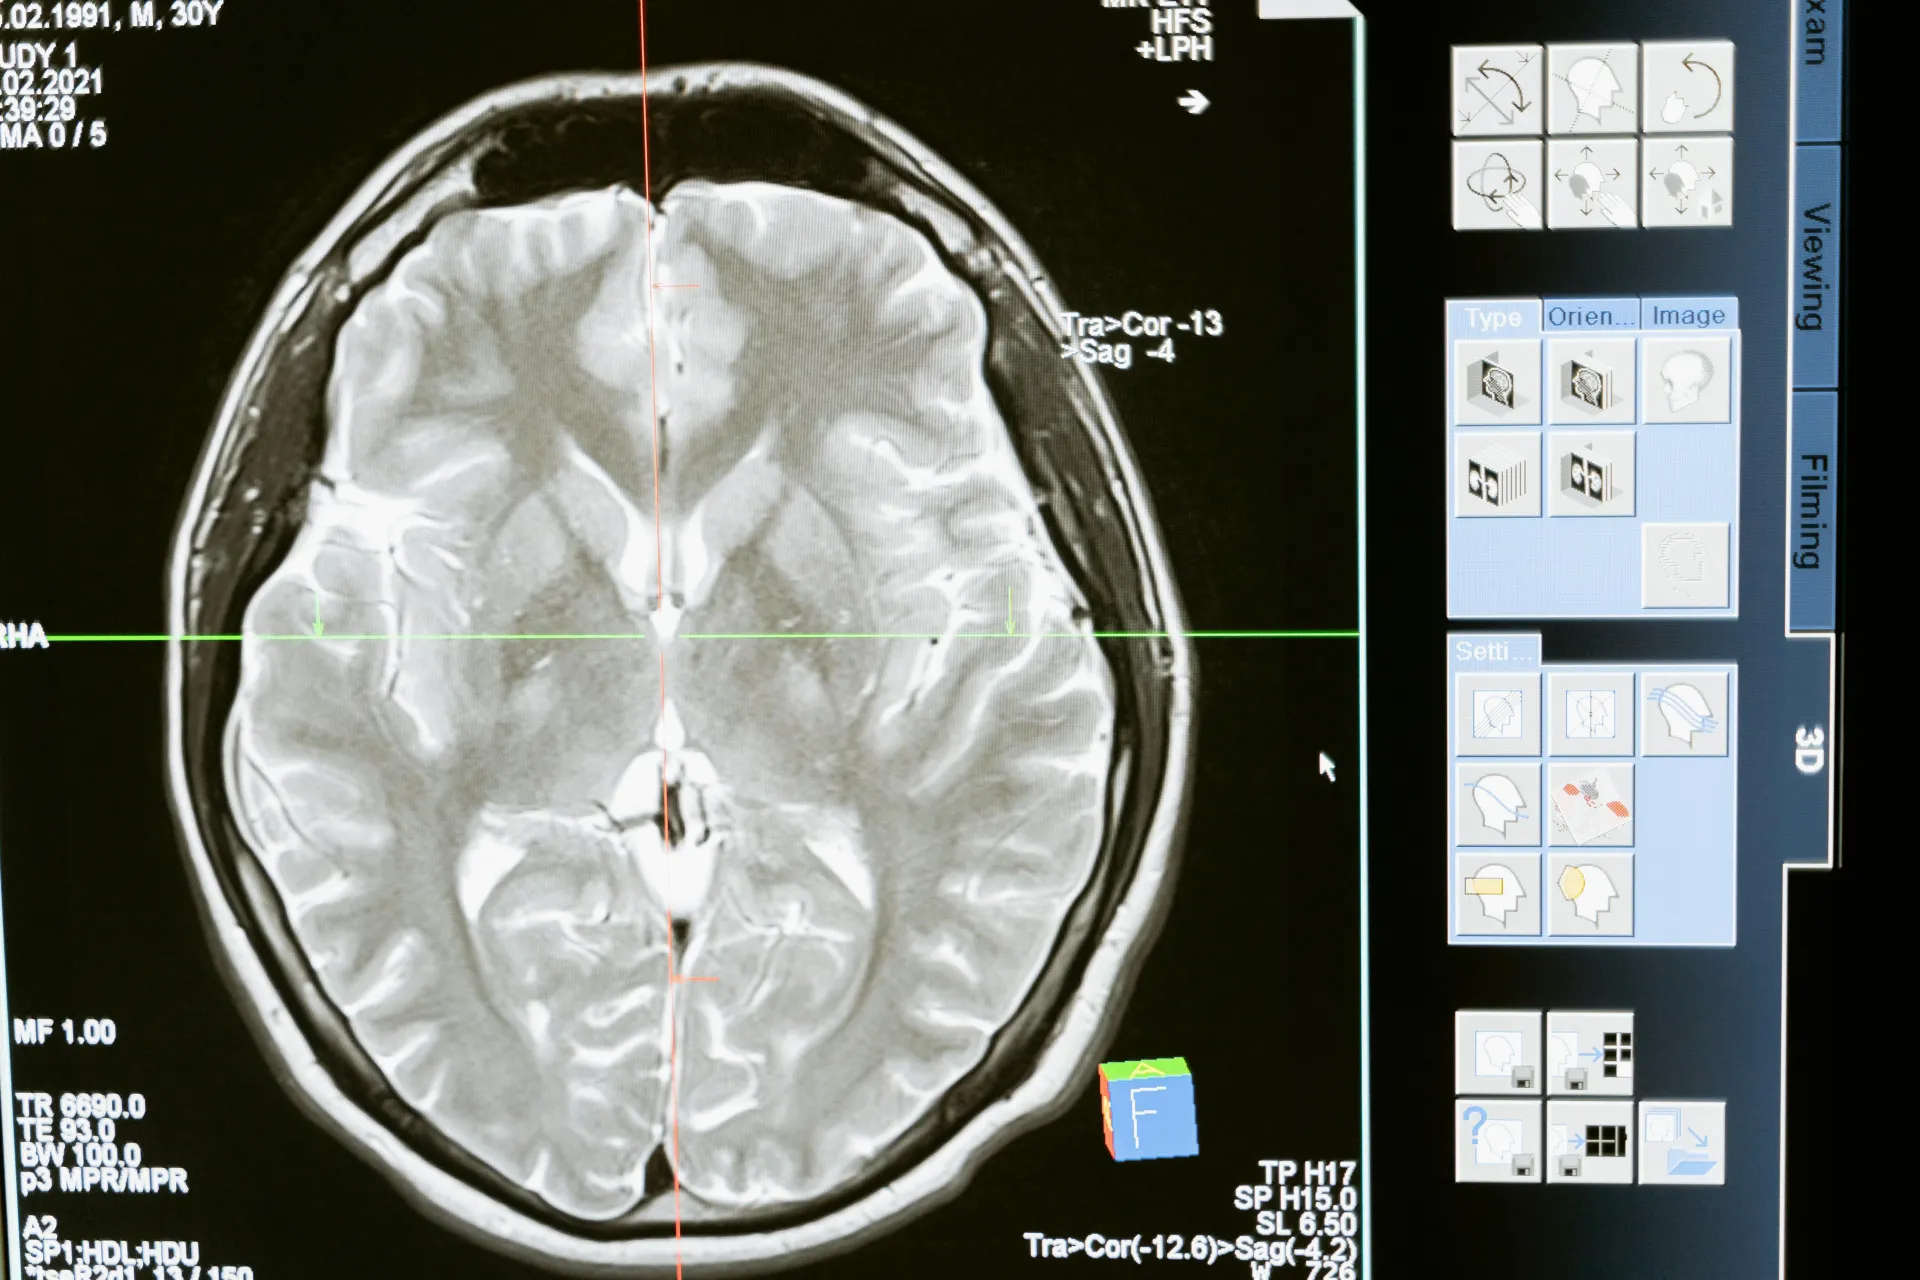

At DCDC, we take an integrated approach to vertigo management, coordinating between neurology and ENT when needed. Our on-site diagnostic capabilities, including brain MRI and coordination with audiology services, allow us to conduct a thorough evaluation and begin treatment promptly. For patients with BPPV, we offer same-day repositioning maneuvers that often provide immediate and lasting relief.

Brain imaging is not required for all vertigo cases but is recommended when clinical features suggest a central nervous system cause, when peripheral causes have been ruled out through examination and testing, when vertigo is accompanied by neurological symptoms such as weakness, numbness, or speech changes, or when symptoms are atypical or not responding to expected treatment. MRI with specific sequences can detect stroke, tumors, multiple sclerosis, and other structural causes. Your specialist will determine if imaging is needed based on your clinical presentation.